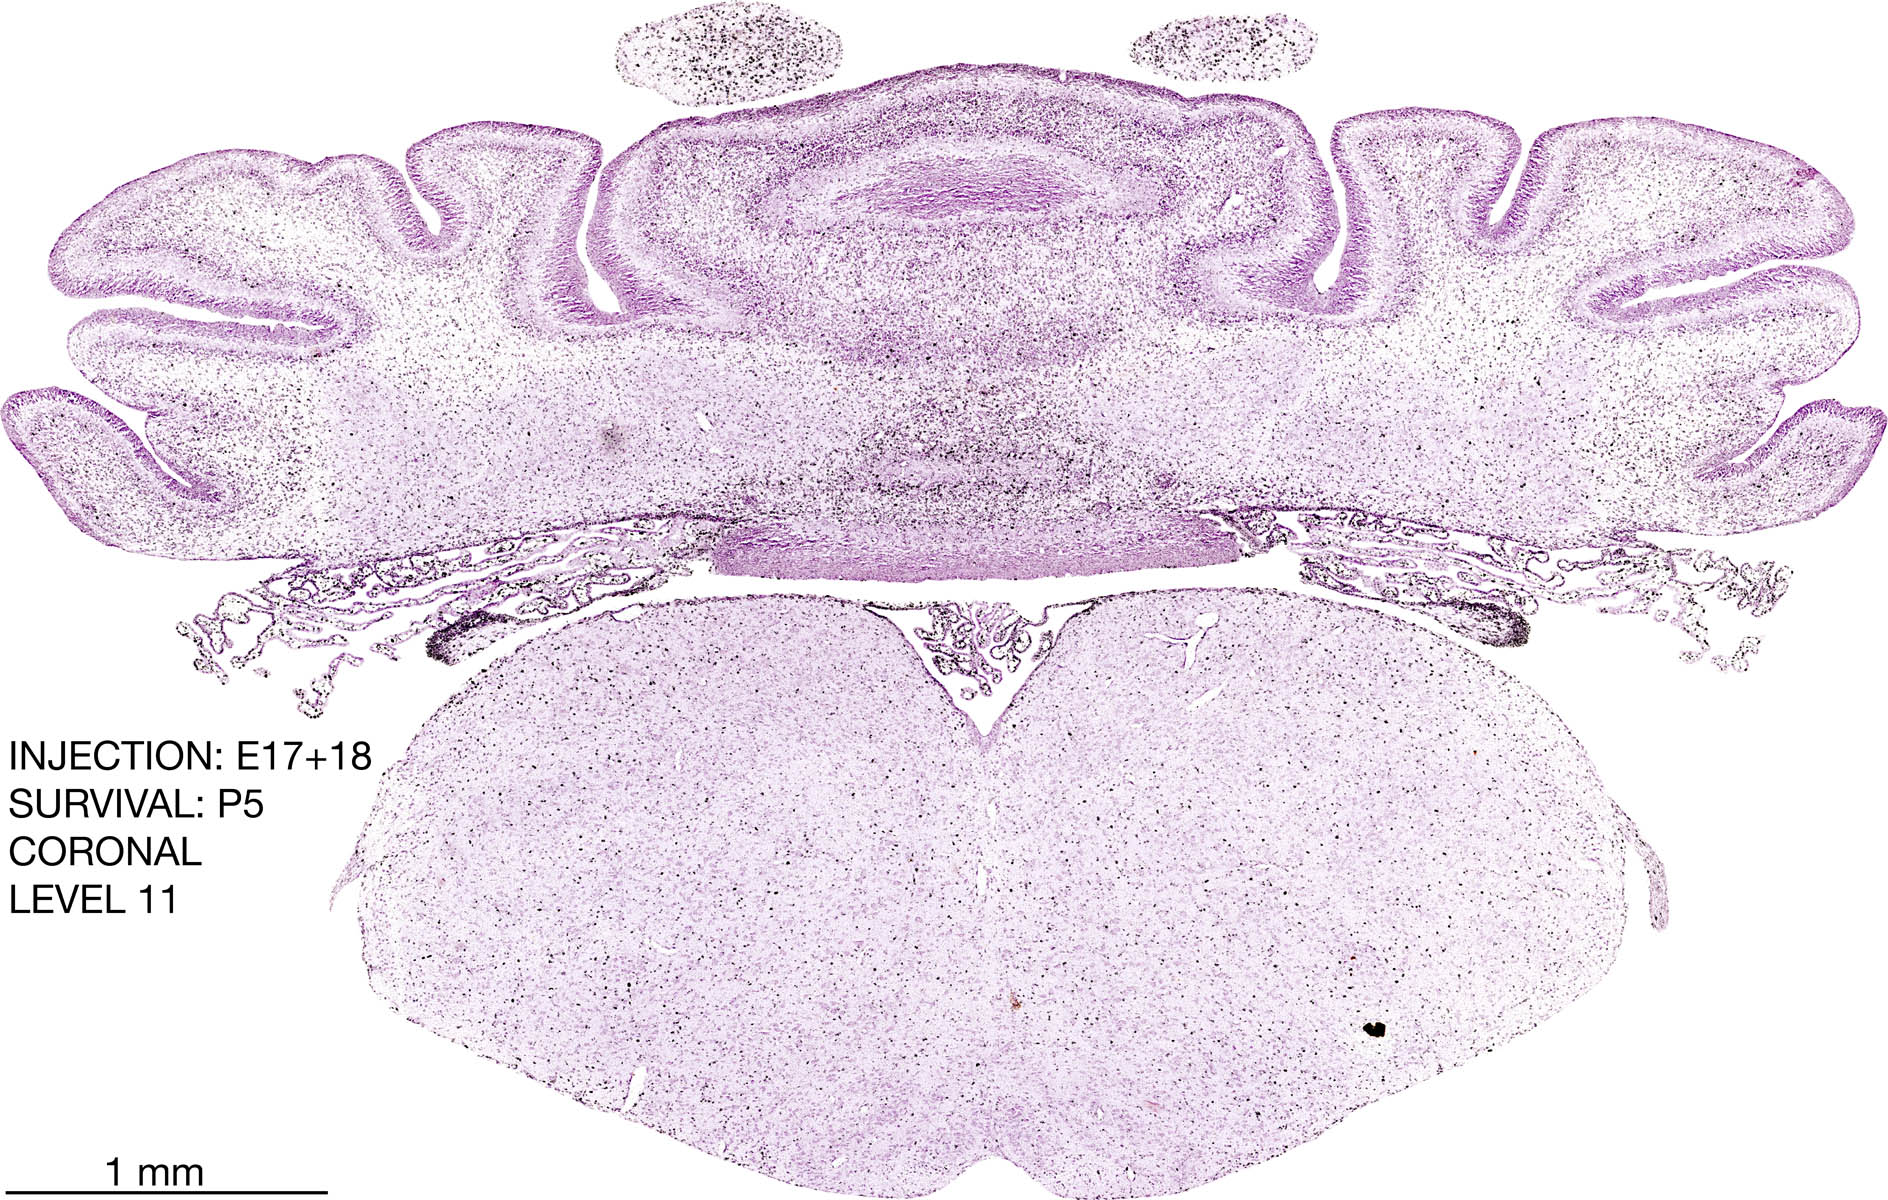

E17+18 P5 Survival The images below are from the brain of a rat that was exposed to tritiated thymidine on E17+18 and survived to P5. Download: Large | High Res Download: Large | High Res Download: Large | High Res Download: Large | High Res Download: Large | High Res Download: Large | High Res Download: Large | High Res Download: Large | High Res Download: Large | High Res Download: Large | High Res Download: Large | High Res Download: Large | High Res Download: Large | High Res Download: Large | High Res Download: Large | High Res Download: Large | High Res Download: Large | High Res Download: Large | High Res Download: Large | High Res Download: Large | High Res Download: Large | High Res Download: Large | High Res Download: Large | High Res Download: Large | High Res Download: Large | High Res Download: Large | High Res